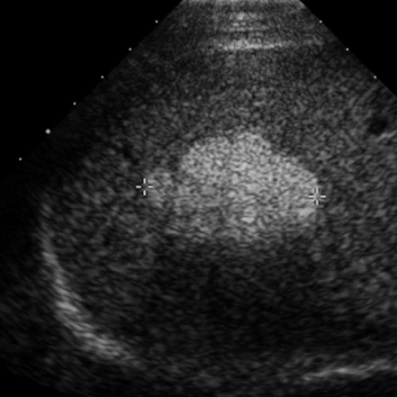

Image echographique de hemangiome : Aspect

echographique typique de hemangiome est lesion hyperechogene

homogene a contour net a renforcement d' echogen posterieure .

Absense de vascularisation au Doppler . Diminue de

l'echoriche a ísoechogenne en compresion ( manoeuvere de

compression )

Aspect echographique

typique d'une hemangiome : Image arrondie

hyperechogene , homogene a bord lisse uniquement au

lobe droit du foie |